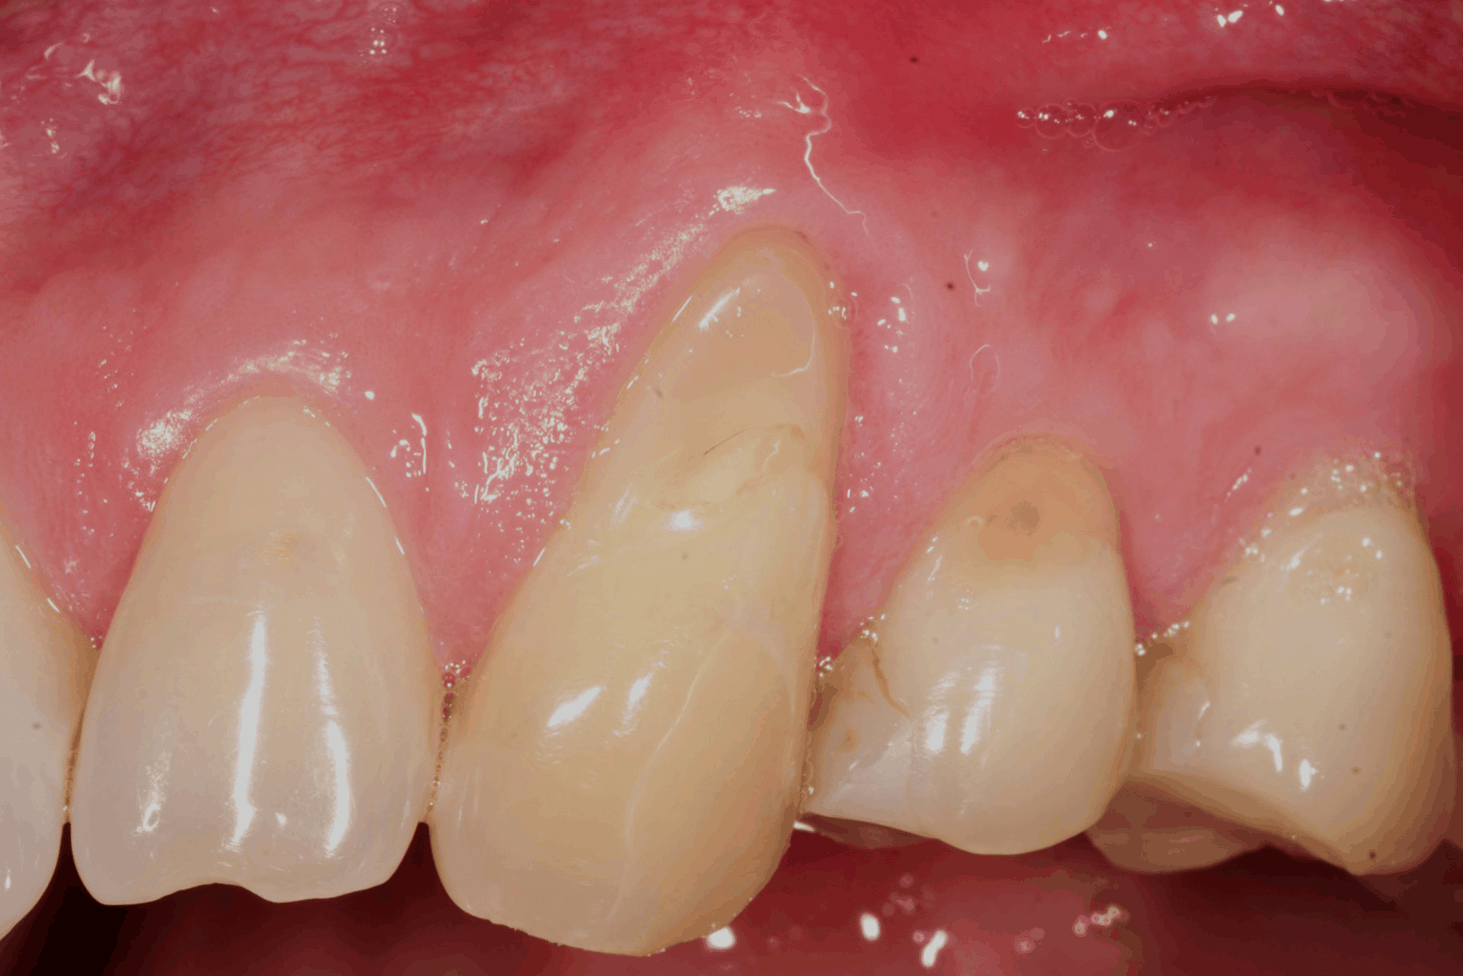

La recessione gengivale è una condizione molto comune. Molti pazienti si accorgono che la gengiva “si ritira”, lasciando scoperta una parte del dente che prima non era visibile. Questo può causare sensibilità, fastidio, problemi estetici e la paura che il dente possa peggiorare nel tempo.

L’innesto gengivale è un trattamento che serve a coprire la radice del dente scoperta e a rendere la gengiva più spessa e resistente.